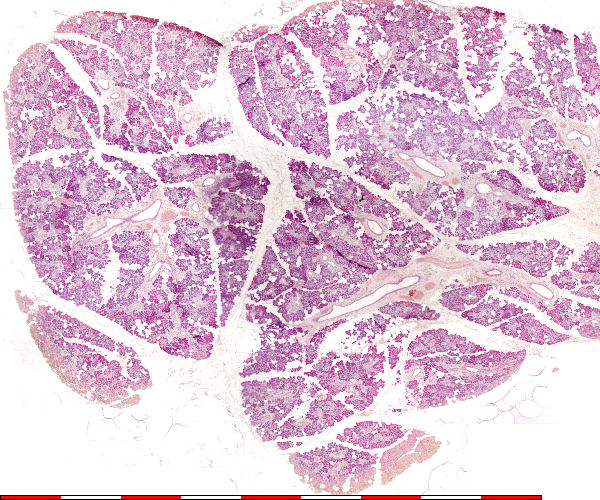

© julie 2008 marius loots